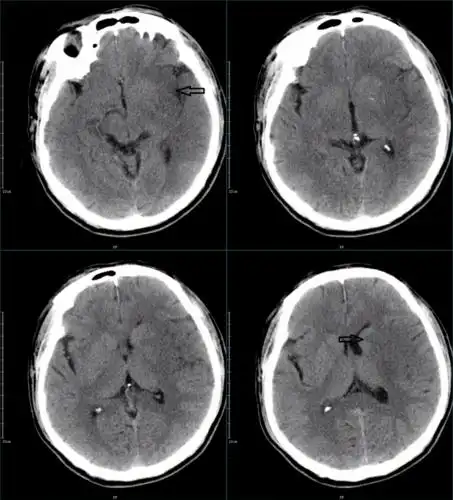

患者入院后头颅ct提示蛛网膜下腔出血,以脑干前方为主,提示后循环

图-:2014年11月24日脑ct.png